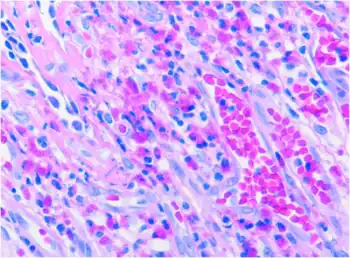

| The dimeric IgA molecule. 1 H-chain, 2 L-chain, 3 J-chain, 4 secretory component | |